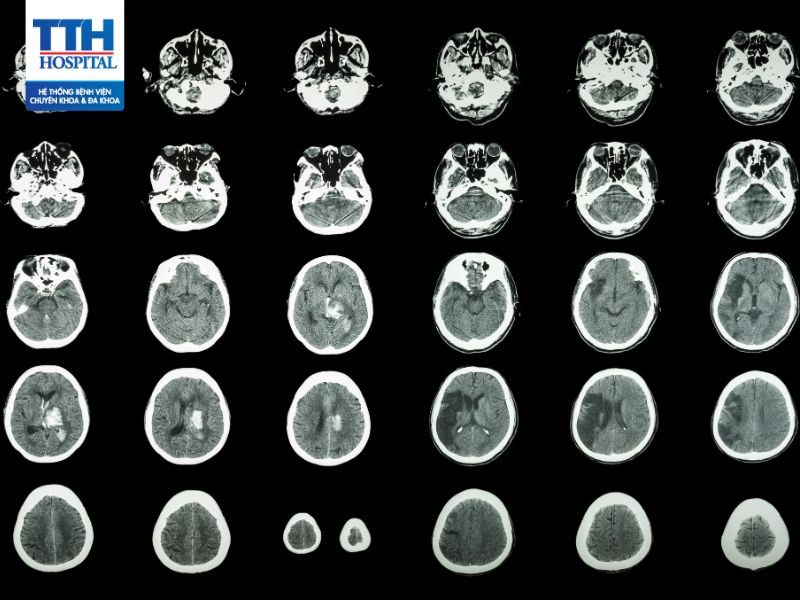

Thần kinh – sọ não

Tai biến mạch máu não hay còn gọi là đột quỵ được xem là một trong những bệnh lý nguy hiểm nhất, nguy cơ tử vong cao nếu không sớm nhận biết triệu chứng tai biến và can thiệp kịp thời.

Tai biến mạch máu não luôn là một thách thức đối với nền Y Học. Theo thống kê của tổ chức Y tế thế giới WHO, tỷ lệ tử vong do tai biến mạch máu não đang đứng thứ ba sau bệnh ung thư và tim mạch.

Tai biến mạch máu não là gì?

Tai biến mạch máu não còn được gọi là cerebrovascular accident (CVA) hoặc stroke, là tình trạng mạch máu cung cấp dưỡng chất và oxy tới một phần của não bị gián đoạn hoặc bị chặn hoàn toàn. Điều này có thể xảy ra do một quá trình gọi là động mạch bị tắc nghẽn (ischemic stroke) hoặc do sự vỡ nứt của mạch máu trong não (hemorrhagic stroke).

- Đột quỵ cấp tính (Ischemic stroke)

Đây là loại phổ biến nhất của tai biến mạch máu não. Nó xảy ra khi một động mạch tới não bị tắc nghẽn bởi mảng bám, cục máu đông, hoặc tắc nghẽn do các tác nhân khác. Khi mạch máu bị tắc, không có oxy và dưỡng chất được cung cấp cho khu vực não bị ảnh hưởng, dẫn đến tổn thương não.

- Tai biến mạch máu não xuất huyết (Hemorrhagic stroke)

Loại này xảy ra khi một mạch máu trong não vỡ nứt, dẫn đến sự chảy máu vào mô não. Điều này gây áp lực lên các mô và tế bào xung quanh, gây ra thiệt hại vùng não và gây ra các triệu chứng như đau đầu cực mạnh.